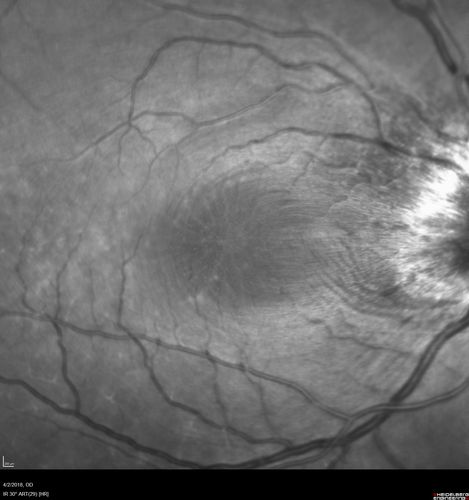

Cat Scratch - Neuroretinitis OD AND retinitis OS - Bartonella henselae positive

27 year old female with exposure to cats and prior fever.  Reports with recent vision loss right eye.  She was treated with doxycycline and within 2 weeks the right eye looks better.  Then she skipped all follow-up visits.  The right eye presented 20/200 and the left 20/16